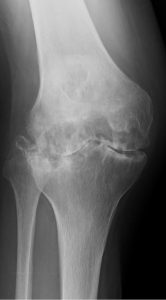

术前(左)和术后(右)关节X光图片病人三年来第一次外出手术

连续142名RA病历(201膝盖)从1997年8月22日到2011年3月16日拥有初级TKA所有程序均由单科外科医生在单一机构进行普通麻醉,所有病人都由同一名医生治病。79名病人口服类固醇,82名病人外科时服甲状腺素22名病人同时使用肿瘤消毒因子对立法处理TKATKA后,59名病人接受了生物治疗初级TKA后,106名病人单从膝部外科手术,其余36名病人额外接受低端联合外科手术,如全流节肢科全科全科全科全科节肢科全科全科全科全科全科全科全科全科全科全科全科全科全科全科全科全科全科全科全科全科全科全科全科全科全科全科全科全科全科全科全科全科全科全科全科全科全科全科全科全科全科全科全科全科全科全科全科全科全科全科全科全科全科全科全科全科全科全科全科全科全科全科全科全科全科全科全科全科全科全科全科全科全科全科全科全科全科全科全科全科全科全科全科全科全科全科全科全科全科全科全科提交者附属机构IRB(机构评审委)批准此项研究

Genesis2(Smith和Nephew,Memphis,TN,USA)在所有例子中都使用假肢类型,1997年8月首次提交115名病人(164个植入式)受难保留TKAs,25名病人(35个植入式)后稳定TKAs,2名病人修改TKAs(2个植入式)。术后第1天,所有案例都应用扩展膝盖支架,并开始ROM运动演练、连续被动运动和增强肌肉活动重生手术第二天允许使用,3周后开始爬楼梯开通T-Cane并忍受上行楼梯后,所有病人都出院

所有病人都评估成日本矫形协会评分(JOA评分)、活动ROM、X光检测结果、RA活动、户外振荡持续时间和移植累积生存率以百分位标度 JOA分数测量疼痛范围 手动肌肉测试 编译能力 爬楼梯能力疼痛标记40分 ROM标记12分 四叉肌肉强度标记20分 步行能力值20分 爬楼梯值8分JOA85或85以上评分被视为优异、70-84良好、60-69公平并低于60穷